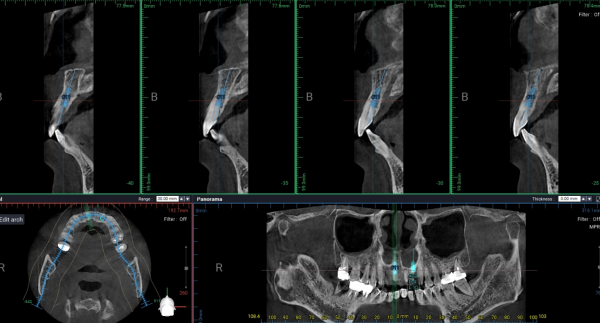

영상 및 구강 검사 소견

파노라마 및 CBCT 분석 결과,

* 전반적인 만성 치주염 소견

* 상·하악 치조골의 광범위한 흡수

* 특히 상악 전치부에서 수직·수평적 골 소실이 현저

* 치근 대비 잔존골 높이 및 폭 모두 제한적

즉, 환자가 느끼는 불편은 앞니였으나

실제 문제는 이미 치조골 단계에서 진행 중인 상태였다.